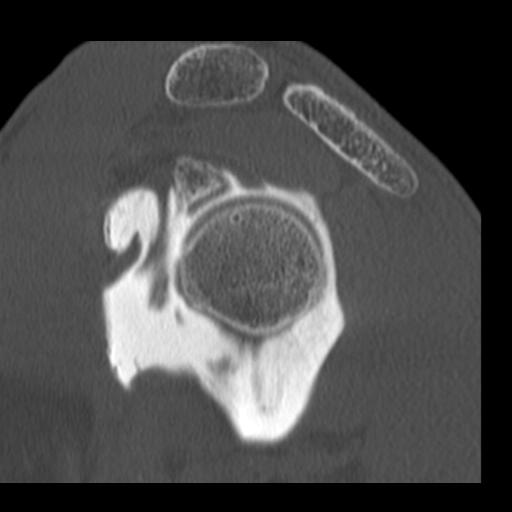

J’ ai dû me faire opérer, oh pas de grand chose, une luxation d’ épaule mais le chirurgien s’ est complètement planté, j’ étais dans un sale état quand enfin j’ ai rencontré un médecin disposé à m’ aider, on me l’ avait bien caché, il a cependant dû me réopérer trois fois.

Les hôpitaux publics me redirigeaient toujours vers l’ établissement qui m’ a raté, le service concerné prétendait que tout allait bien, que la greffe n’ avait pas prise mais qu’ elle ne bougeait pas ( examen réalisé au papier calque). Je repartais avec des ordonnances contre la douleur de plus en plus gonflées, un jour on m’ a demandé si c’ était pour un cheval lorsque j’ ai voulu reproduire l’ une d’ elles.

J’ ai tenté de porter plainte contre l’ hôpital, il parait que ça ne se fait pas, ça m’ a coûté des nerfs et pas mal d’ argent pour des rapports qui informent que la greffe était mal positionné, qu’ elle ne pouvait pas prendre mais que l’ on ne peut cependant pas considérer qu’ il s’ agit d’ une erreur. De quoi s’ agit t’ il alors ? D’ une expérience ? Est ce que j’ ai servi de cobaye ? Je n’ en saurai jamais plus, le dernier expert m’ a conseillé d’ abandonner, que j’ allais me noyer dans cette affaire.